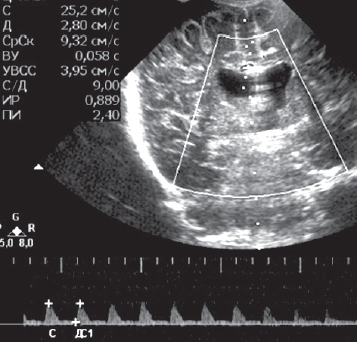

В статье кратко приведены литературные данные и описание клинического динамического наблюдения пациента с тяжелым гипоксическим повреждением головного мозга (от неонатального периода до 4-го месяца жизни) в условиях отделения реанимации и интенсивной терапии новорожденных. Представлены описание клинической картины, особенности пароксизмальных состояний и антиэпилептической терапии, динамика данных нейровизуализации, электроэнцефалографических феноменов, регистрируемых у пациента с церебральной депрессией и структурными церебральными повреждениями. Показана значимость электроэнцефалографического исследования в условиях отделения реанимации как информативного метода оценки церебральной активности у детей раннего возраста с синдромом угнетения центральной нервной системы. Дезорганизация фоновой активности, свидетельствующая о структурных церебральных повреждениях, длительное персистирование медленноволновой активности, выявление эпилептических изменений в виде генерализованных вспышек заостренных волн в диапазоне тета, паттерн альфа-комы, впоследствии сменившийся супрессией фонового паттерна у пациента, являются типичными электрофизиологическими нарушениями, регистрирующимися при тяжелой гипоксической энцефалопатии. В условиях ограничения возможностей визуальной диагностики пациента с нарушением сознания электроэнцефалография остается единственным методом получения информации о функциональном состоянии головного мозга, а данные, полученные при исследовании, — важным прогностическим критерием.